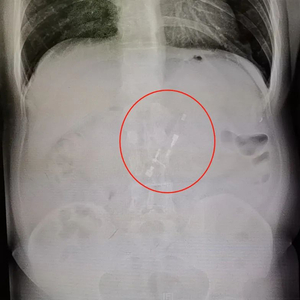

经过相关检查,陈叔的X光片显示,他的胃里有个白色条形物质——正是他几天前吞下的打火机。他这才紧张起来,连忙到消化内镜中心去做下一步的异物取出术。

X光片显示,胃里有个白色条形物质。通讯员供图

胃里的异物可能正是几天前吞下的打火机。通讯员供图